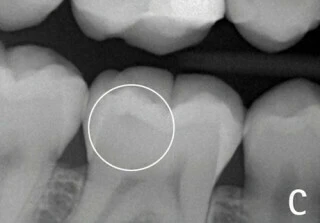

Hình 4: Vị trí tiếp giáp men-ngà (khoanh tròn) có sâu hay không sâu? Rất khó để nhận định trường hợp sâu mặt nhai mới đi qua lớp men răng chớm vào lớp ngà so với trường hợp không sâu răng nếu đánh giá trên phim X-quang tại chỗ.

Hiệu ứng mach band trong X-quang nha khoa là ảo ảnh thị giác gây ra một vùng thấu quang giả nằm giữa hai cấu trúc có mật độ quang học khác nhau (gây ra mức độ cản quang khác nhau), ví dụ như men răng và ngà răng. Một đường mỏng nhìn thấy được ở bề mặt ngà răng và sâu răng có thể nhầm lẫn với nhau. Hiện tượng Mach band thông thường chỉ giới hạn là một đường mảnh 0.5mm dưới đường nối men-ngà (4). Có thể thấy điều này rõ ràng hơn ở ranh giới giữa vật liệu phục hình (đặc biệt có chứa kim loại) nằm giữa men và ngà răng. Hiệu ứng này thường gây chẩn đoán sai thành sâu răng thứ phát hoặc làm nha sĩ đánh giá sai về độ lớn của tổn thương sâu răng. Nó cũng gây chẩn đoán thiếu trong trường hợp gãy chân răng theo chiều ngang do sự khác biệt về cường độ tia (radiographic intensities) của răng và xương. (5)